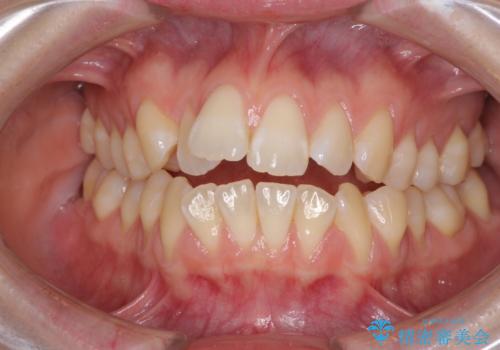

上下前歯が接触しない オープンバイトをインビザラインで改善

オープンバイト(開咬)を非抜歯インビザラインで治す